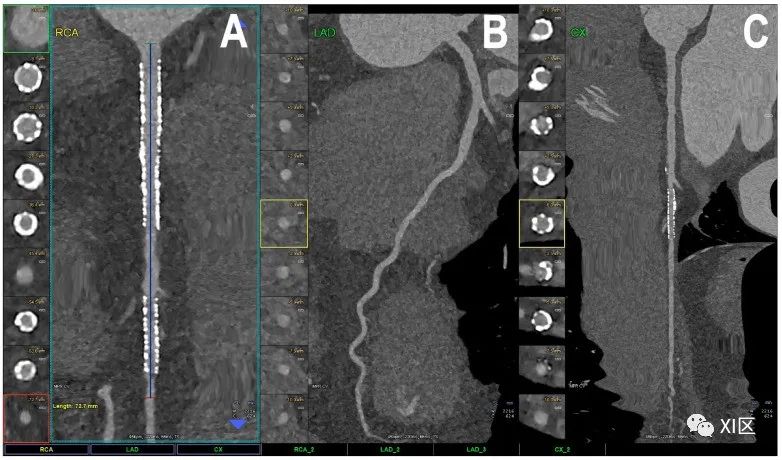

带有多个支架的完整冠状动脉树的心脏PCCT示例。图中显示的是随访时带有多个支架的患者的完整冠状动脉(A-C)。在右冠近端和中段(A)有两个支架,在左缘支(C)有一个支架;左前降支(LAD;(B))正常,没有任何可检测到的动脉粥样硬化疾病。所有支架的内支架和内腔都清晰可见,这在没有传统EID心脏CT上通常不能清晰显示。